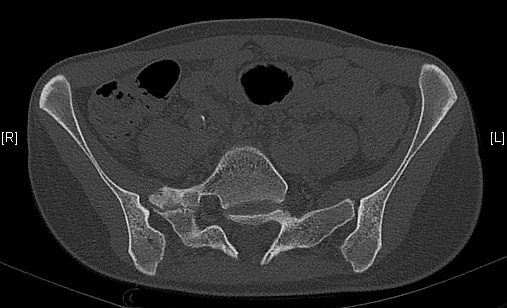

Néo-articulation transverso-sacrée droite

Spina bifida occulta